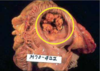

Hemorrhagic Pericarditis

Fibrous pericarditis + hemorrhage

W/o inflammation, blood in pericardial sac = hemopericardium

Hemorrhagic pericarditis

Surface of heart with hemorrhagic pericarditis has roughened, red appearance

Most likely to occur with metastatic tumor & TB